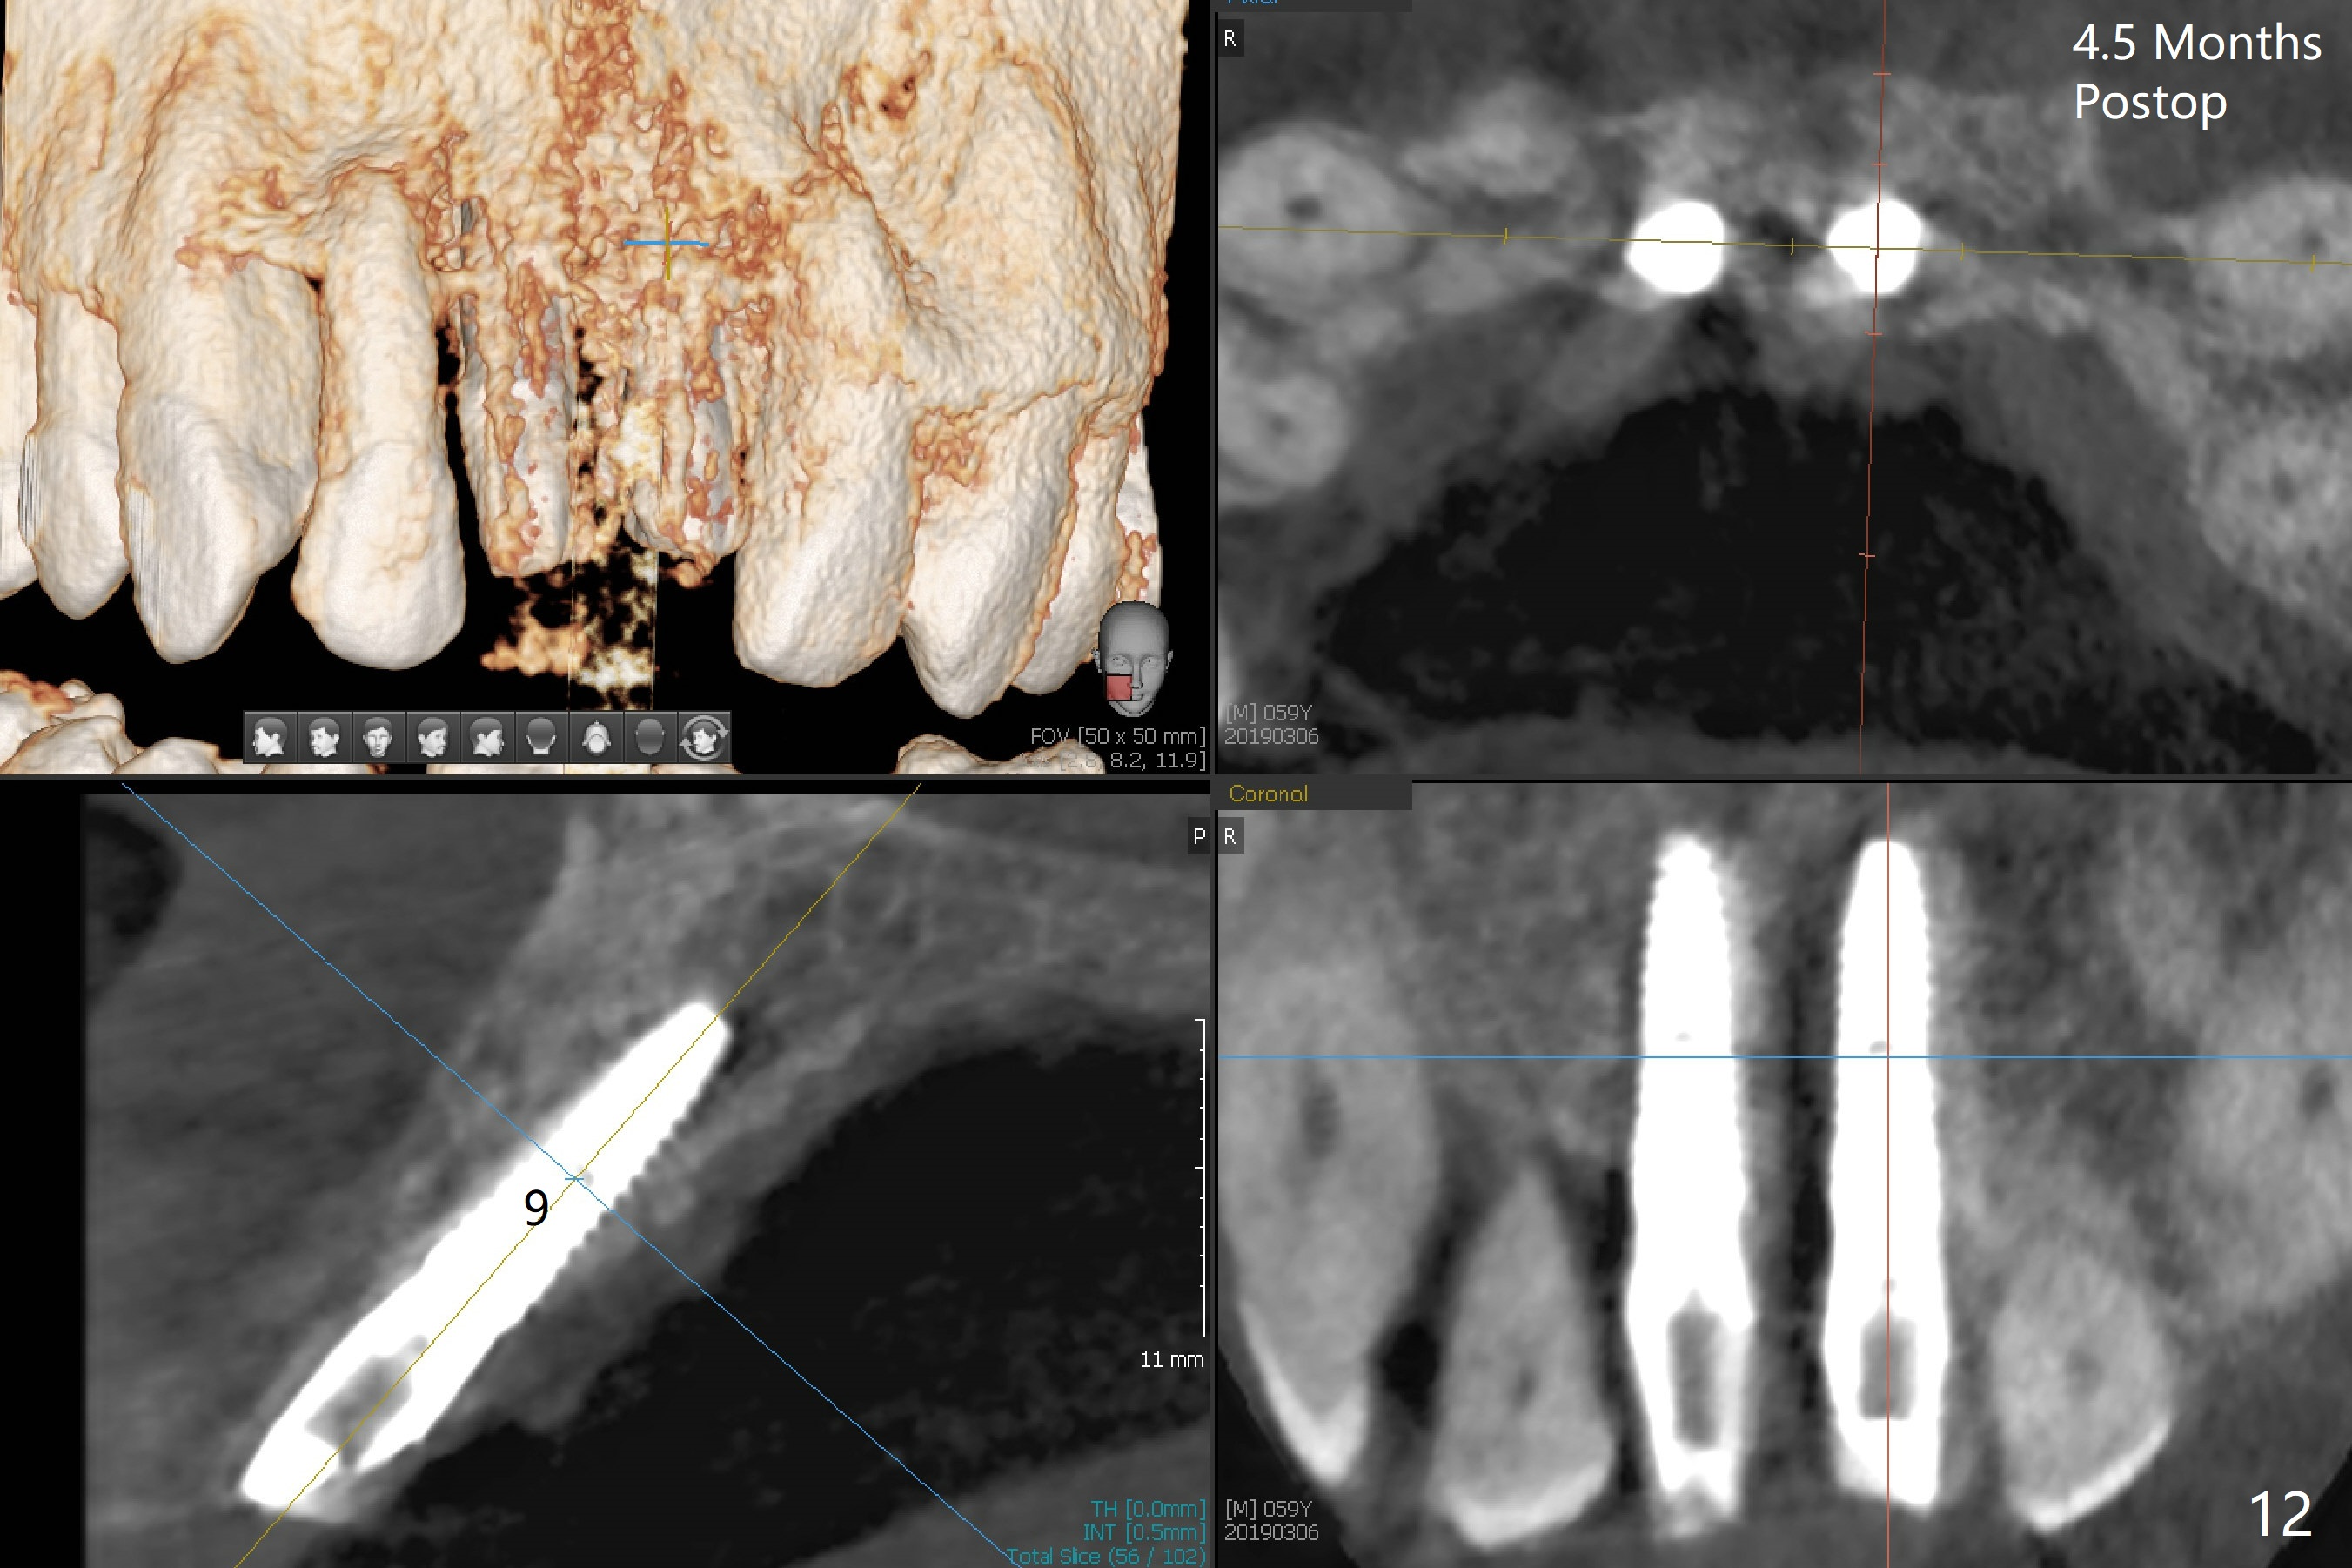

There is no buccal plate at #8 or 9 when the teeth are extracted as well as severe soft tissue defect at #8. Osteotomy is initiated as palatal as possible (Fig.1). When 3.5x13 mm implants are placed initially, the one at #8 is supracrestal (Fig.2 ^). To reduce the chance of peri-implantitis, the implant is placed deeper (Fig.3 (~2 mm implant threads exposed buccally)) with placement of sticky bone around the implants and 4.5x5.5(4) mm abutments (Fig.3 *). The buccal soft tissue defect #8 is repaired with a piece of PRF membrane (Fig.4 *), followed by periodontal dressing. Smaller 2-piece implants (3 mm, IBS) with smaller abutments (4 mm) may further reduce chance of periimplantitis and easy buccopalatal reduction of the abutments for restoration. The periodontal dressing remains stable 7 days postop (Fig.5) because it wraps around the abutments (Fig.6 A). By the time the periodontal dressing gets loose, #8 buccal soft tissue defect should be healing. When breaking-down periodontal dressing is removed 17 days postop, the coronal abutments and bone graft are exposed; after fabrication of provisional crowns (Fig.7), periodontal dressing is re-applied buccally. When the second dressing dislodges 5 weeks postop, the buccal soft tissue appears to reduce (Fig.8). Raising flaps may be less traumatic. A piece of bone graft is being extruded 4 months postop (Fig.9 >). After the abutments change from 4.5x5.5(4) to 4.5x7(3) mm, new temporary crowns are fabricated (Fig.10 (4.5 months postop)). CT shows apparent buccal bone at #8 and 9 (Fig.11,12). How to improve cosmetic?